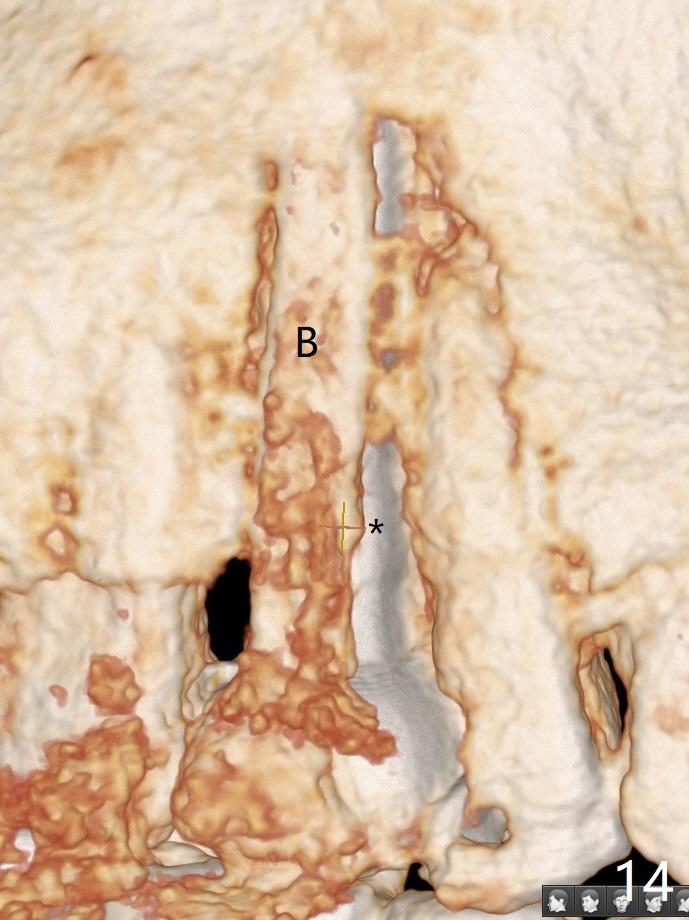

In fact there is a small buccal fistula, which is communicated with the underlying implant threads. Although preop CT shows that the buccal crest is lower than the palatal (3.8x13 mm, Fig.10 P) one, intraop finding of missing buccal plate should dictate a shorter implant (Fig.11) or onlay graft to avoid periimplantitis. Regeneration of the bone plate is limited. Later the fistula disappears with formation of a concavity (Fig.13). There is no symptom. Is bone graft necessary with a remote incision? 3-D images of CT taken 1 year 5 months post cementation show possible mesiobuccal and distopalatal bony defects (Fig.13-16). It is possible that bone graft was placed enough palatal (Fig.16). DO composite at #3 is redo satisfactorily (Fig.17 *).